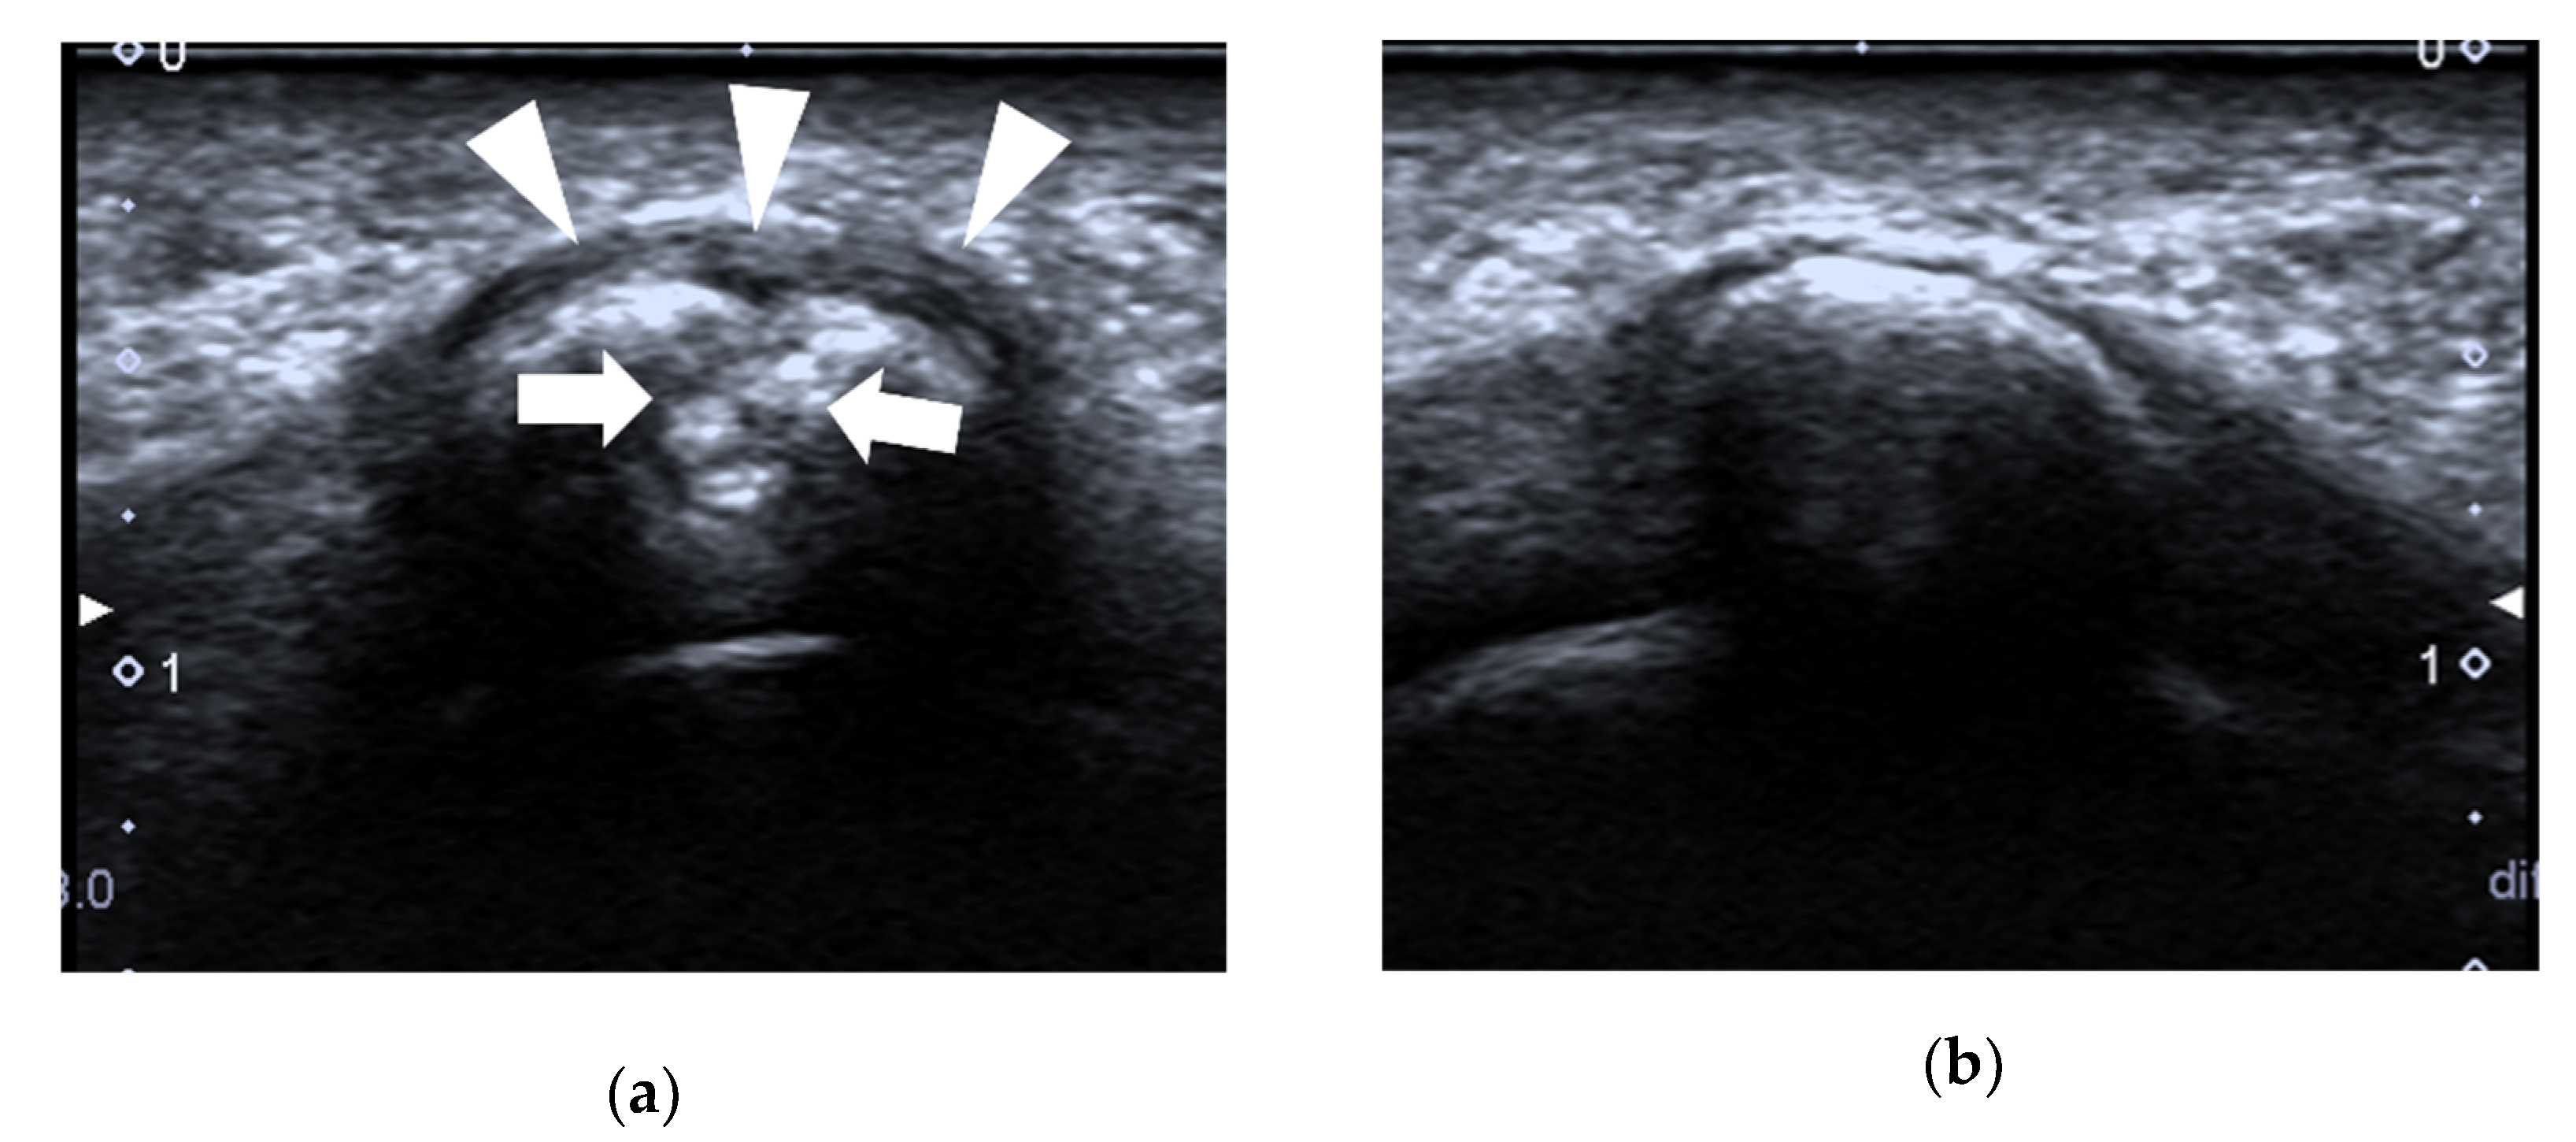

4.1.1. Plantar Plate Tear

| Plantar plate tear | 2nd MTP joint | discrete anechoic cleft or area of heterogeneous echotexture in the plantar plate |